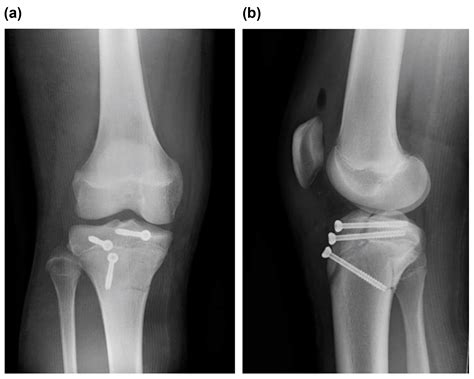

However, if the fragment is displaced or if the knee joint is compromised, surgical intervention is mandatory. The surgical procedure typically involves:

• Open Reduction Internal Fixation (ORIF): The surgeon makes an incision to visualize the bone fragment.

• Hardware Placement: The loose piece of bone is secured back to the main tibia using screws, wires, or specialized anchors.

• Tendon Repair: If the patellar tendon is damaged during the avulsion, it is repaired and reinforced during the procedure.